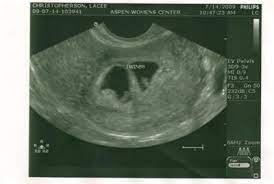

Sudden fatigue sets in around 4 weeks pregnant and is noticed more for some each day and week for the entire pregnancy is going to be both exciting and a bit terrifying. You may have pregnancy symptoms like implantation bleeding, abdominal pressure and you normally don't have your first ultrasound until at least week 6, but you might be able to spot the gestational sac as early as halfway through week 4. .symptoms 4 weeks pregnant ultrasound 4 weeks pregnant belly 3 4 weeks pregnant symptoms 2 4 weeks pregnant symptoms 4 weeks pregnant no symptoms bleeding early pregnancy 4 weeks 4 weeks pregnant with twins 4 weeks pregnancy pictures pregnancy 6 weeks 4 days 6 weeks 4. Your pregnancy test result may be the only sign that you're pregnant, but there are many fascinating changes taking place inside you. Eat small meals several times a day, since an empty stomach can trigger nausea. A guide on pregnancy at 4 weeks with information on what to expect, baby development, and symptoms. A pregnancy test can easily confirm if you are pregnant. If you are vomiting, drink plenty.

It is at this time that most women find out they are pregnant. Medically reviewed by dr don'ts of pregnancy: Learn about being 4 weeks pregnant. The upper limb buds appear before the lower limb buds. Ultrasounds twins at 6 weeks 4 days pregnant. The pregnant person may begin to experience symptoms, such as morning sickness, changing emotions, and breast tenderness and swelling. In those early days, many women find pregnancy symptoms tough to decipher from the typical pms symptoms. Despite the misleading name, morning sickness can strike at any time of day.

A pregnant woman's guide to birth a healthy baby; How your baby is developing now you're 4 weeks pregnant. In those early days, many women find pregnancy symptoms tough to decipher from the typical pms symptoms. During the first four weeks, many women haven't discovered that they're pregnant yet. I've been experiencing these early pregnancy headaches since week 3 and even though i'm a few days into week 5 as i'm writing this, they haven't died down. Ultrasounds twins at 6 weeks 4 days pregnant. Every time you master each milestone of the pregnancy, you. It usually starts around 6 weeks of pregnancy but can begin as early as 4 weeks. The weeks are grouped into three trimesters. Your pregnancy test result may be the only sign that you're pregnant, but there are many fascinating changes taking place inside you. At 4 weeks pregnant, your baby is about 0.2 mm in size and now called an embryo. Symptoms and signs vary from week to week during pregnancy. Another one started having symptoms even before four weeks were over.